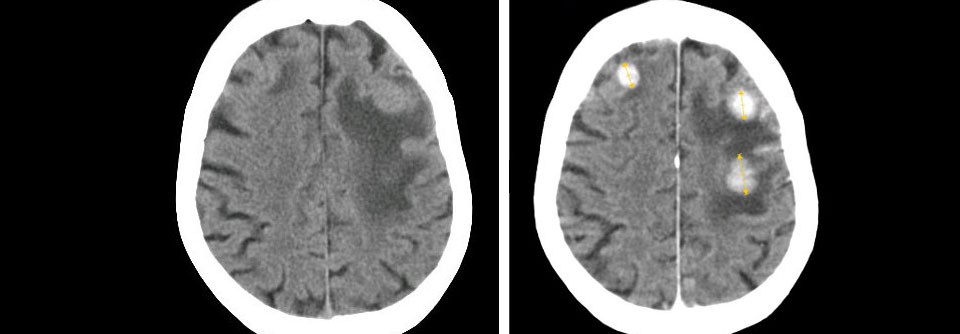

Bei kleinen Metastasen gilt weiterhin die stereotaktische Bestrahlung als sinnvoll. Bei kleinen Metastasen gilt weiterhin die stereotaktische Bestrahlung als sinnvoll. © iStock/Mark Kostich

Die AGO Mamma hat aktuell zudem die Empfehlungen zum Vorgehen bei singulären und Oligometastasen zusammengefasst und präzisiert: Unverändert raten die Expert:innen dazu, Metastasen bis maximal 4 cm stereotaktisch zu bestrahlen (LoE GR AGO 1b B ++). Besteht eine Indikation zur Resektion, gilt für beide…